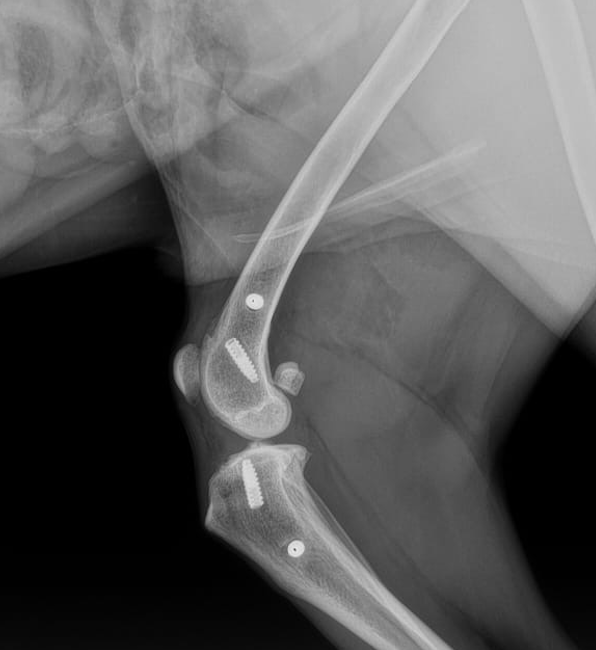

Aujourd’hui, nous vous partageons le suivi (vidéo + radio) de Horus, un Whippet âgé de 10 ans, 𝘂𝗻 𝗮𝗻 𝗮𝗽𝗿𝗲̀𝘀 𝘂𝗻𝗲 𝗰𝗵𝗶𝗿𝘂𝗿𝗴𝗶𝗲 de reconstruction du ligament croisé crânial du côté droit.

Pour ce cas, c'est le Z-lig® 32 / 17 (UHMWPE - 4 000N) qui a été utilisé et 4 vis canulées (ø 4.5mm) qui ont été mises en place pour maintenir l'implant.

Lors d'un examen clinique et radiographique à 1 an post opératoire, voici le constat:

✅ Grasset stable.

✅ Amplitude de mouvement complète.

✅ Masse musculaire retrouvée.

✅ Pas de migration des vis.

✅ Tunnels osseux intacts.